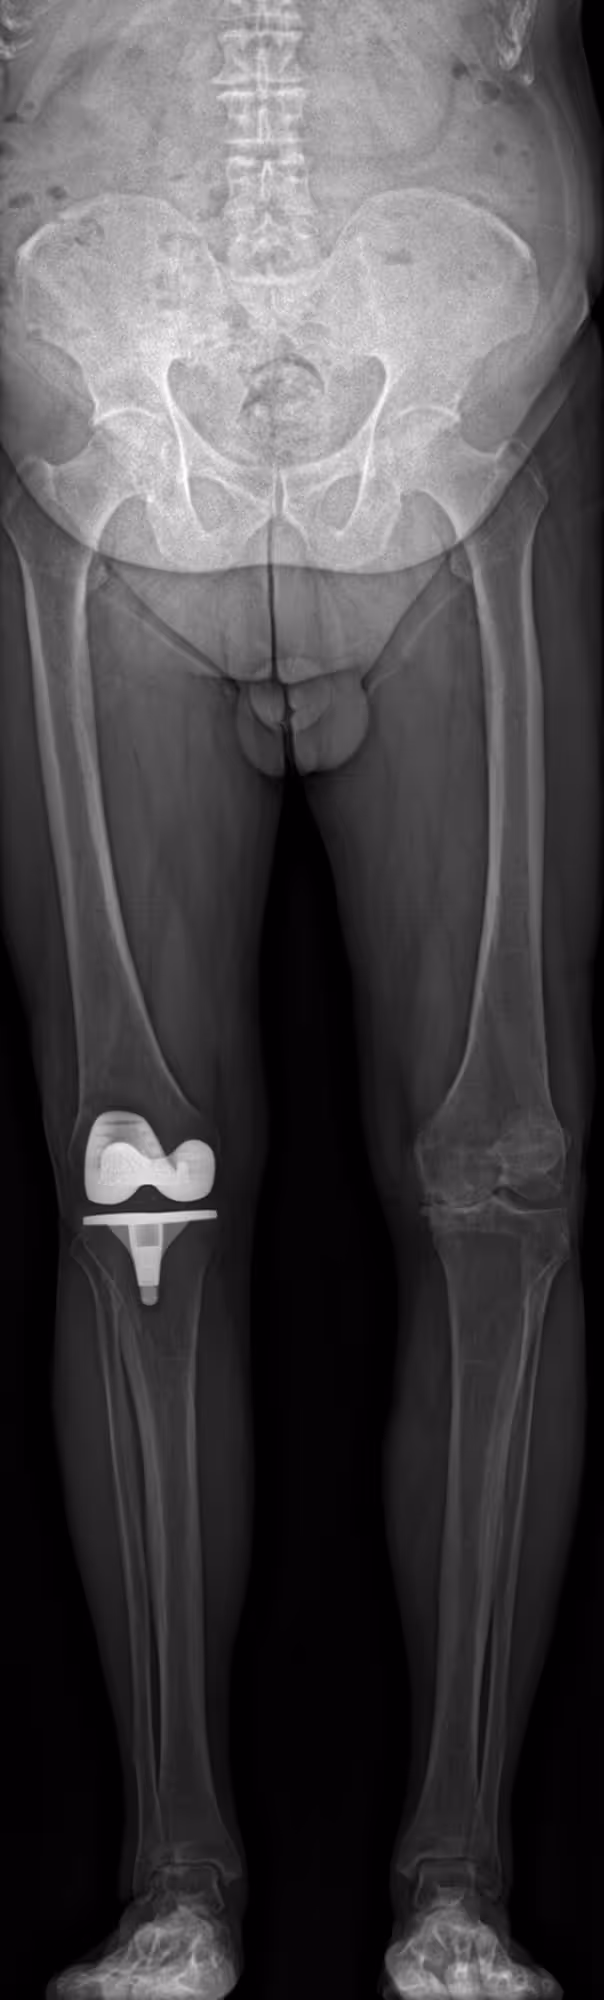

A 78-year-old male presenting with left medial knee pain, undergoing evaluation prior to potential prosthesis placement

BoneMetrics measured a left genu varum deformity, consistent with varus malalignment of the knee.